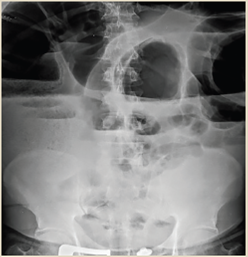

Paciente del sexo masculino, de 79 años, inició su padecimiento actual con estreñimiento de 10 días de evolución; se agrega náusea, vómito, distensión y dolor abdominal. Antecedentes relevantes: diabetes mellitus tipo 2 en control, negó antecedentes quirúrgicos; antecedentes de trauma abdominal cerrado durante la infancia posterior al cual presentó varios cuadros de distensión, y dolor abdominal difuso y estreñimiento crónico. A la exploración física dirigida se observó distensión abdominal, silencio abdominal, se palparon impresiones aparentemente de asas intestinales predominantemente en flanco e hipocondrio izquierdos; doloroso a la palpación profunda, con abdomen en tabla, signo de rebote no valorable, hipertimpanismo a la percusión. Estudios paraclínicos reportaron acidosis metabólica leve con déficit de base. Las radiografías de tórax y abdomen evidenciaron distensión importante del colon transverso hasta el ángulo esplénico e incremento del patrón de distribución aérea, así como colon sigmoides dilatado y desplazamiento e interposición de asas sobre colon ascendente y ángulo hepático con niveles hidroaéreos (figuras 6 y 7). Se integró diagnóstico de probable megacolon secundario a vólvulo intestinal complicado, con datos de peritonitis e isquemia intestinal. Se indicó laparotomía exploratoria de urgencia; como hallazgos quirúrgicos se obtuvieron colon descendente y sigmoides distendidos, diámetro máximo de 20 cm y 100 cm de longitud (figura 8), laxitud marcada de sus medios de fijación, vólvulo a nivel de transición de colon descendente y sigmoides, así como múltiples adherencias en el trayecto del colon transverso, descendente y sigmoides (figura 9). Se realizó procedimiento de Hartmann con colostomía de colon transverso.

Figura 7 AP de abdomen. Colon sigmoides dilatado, desplazamiento e interposición de asas sobre colon ascendente y ángulo hepático, niveles hidroaéreos